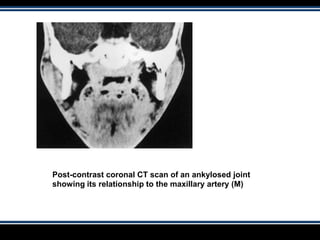

Post-contrast coronal CT scan of an ankylosed joint

showing its relationship to the maxillary artery (M)